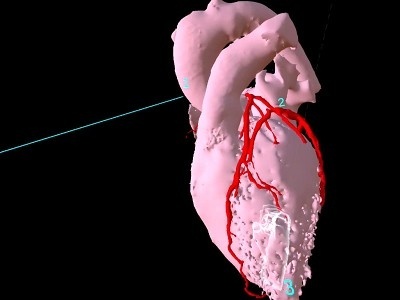

今回の授業ではこの1年間に習った内臓や筋、血管や神経といった臓器がどのように体内に存在し、その内部構造がどうなっているのかを、VR(3次元の仮想空間)で理解していきます。

しかし、このVRを用いた授業では、「へえ~」「なるほど」と仮想空間にある臓器を持ったり、位置の確認をしたり、のぞき込んだりと楽しく授業を受けていました

- 心臓